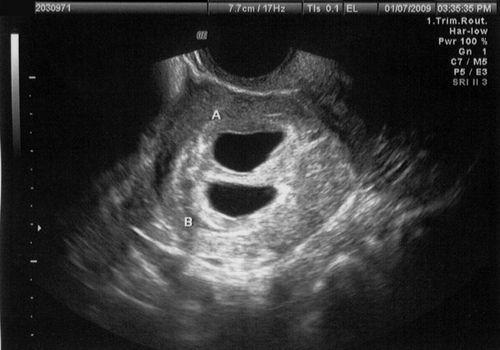

超声图像显示两个妊娠囊

Chris Sternal-Johnson /盖蒂图片社